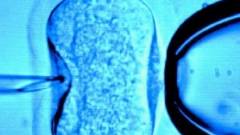

A proposal by fertility researchers to “harvest” female gametes, “ova,” from the dead bodies of aborted children to create in vitro embryos in the lab has created a small buzz among the pro-life websites, blogs and Facebook in the last couple of days. But the buzz is over a story that appeared in the Daily Mail nearly ten years ago, about research that has very likely moved along considerably in that time. In July 2003, the Daily Mail wrote about the work of a team of researchers from Israel, revealed at the annual conference of the European Society of Human Reproduction and Embryology in Madrid. These researchers had successfully cultivated ovarian follicles in the lab, keeping them alive for several weeks. The tissue, the part of the female reproductive system that gives rise to ova, had been taken from seven babies aborted at between 22 and 33 weeks gestation. It was cultivated in a mixture of chemicals and hormones over four weeks and the follicles matured to the stage just prior to the production of gametes.

Dr. Tal Biron-Shental, from Meir Hospital in Kfar Saba, Israel, was quoted by the Mail, as well as the BBC and a few other outlets, conceding that the concept of taking ovarian tissue from aborted babies “was controversial”. In fact, her quotes revealed much about the direction the abortion ideology has taken; one of pure, ice-cold utilitarianism.

“I’m fully aware of the controversy about this - but probably, in some place, it will be ethically acceptable,” Biron-Shental said. “There is a shortage of donated oocytes (eggs) for IVF - oocytes from aborted fetuses might provide a new source for these.

“There are a huge amount of follicles in the fetal ovary.”